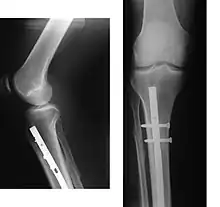

An intramedullary rod, also known as an intramedullary nail (IM nail) or inter-locking nail or Küntscher nail (without proximal or distal fixation), is a metal rod forced into the medullary cavity of a bone. IM nails have long been used to treat fractures of long bones of the body. Gerhard Küntscher is credited with the first use of this device in 1939,[1][2] during World War II, for soldiers with fractures of the femur. Prior to that, treatment of such fractures was limited to traction or plaster, both of which required long periods of inactivity. IM nails resulted in earlier return to activity for the soldiers, sometimes even within a span of a few weeks, since they share the load with the bone, rather than entirely supporting the bone.[3]

Although stainless steel was used for older IM nails, titanium has several advantages, including lower mechanical failure rates and improved biocompatibility.[6] A more significant problem with earlier designs was their failure to prevent collapse or rotation in inherently unstable fractures. This was addressed by the introduction of the concept of 'locking' the nails, where bolts on each end of the nail fix it to the bony cortex, preventing rotation among the fragments. This led to the emergence of locked IM nailing, which is the standard today.[3]